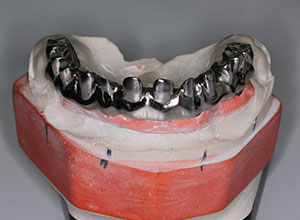

La prótesis dental híbrida consta de una estructura de metal recubierta de varias capas de porcelana blanca y rosa que dan la estética de los dientes y de la encía.

Dicha estructura se atornilla sobre los implantes que se han colocado previamente en el hueso mediante la cirugía.

Esto se hace mediante unos tornillos intermedios que fijan toda la estructura y sellan el espacio entre la prótesis y los implantes.

Por último, la entrada de estos tornillos a través de la prótesis se sella mediante el uso de teflón y resina, como si se estuviera realizando una obturación o empaste dental.

Esta estructura de metal irá recubierta de una resina compuesta de laboratorio, que es la que va a dar la estética de los dientes y de la encía rosa.